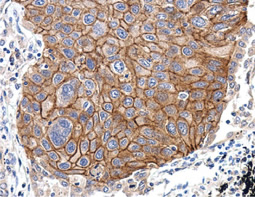

![Her2 / ErbB2 antibody [C2C3], C-term](/upload/media/research/Cancer/Oncogenes/Oncoproteins_07.jpg)